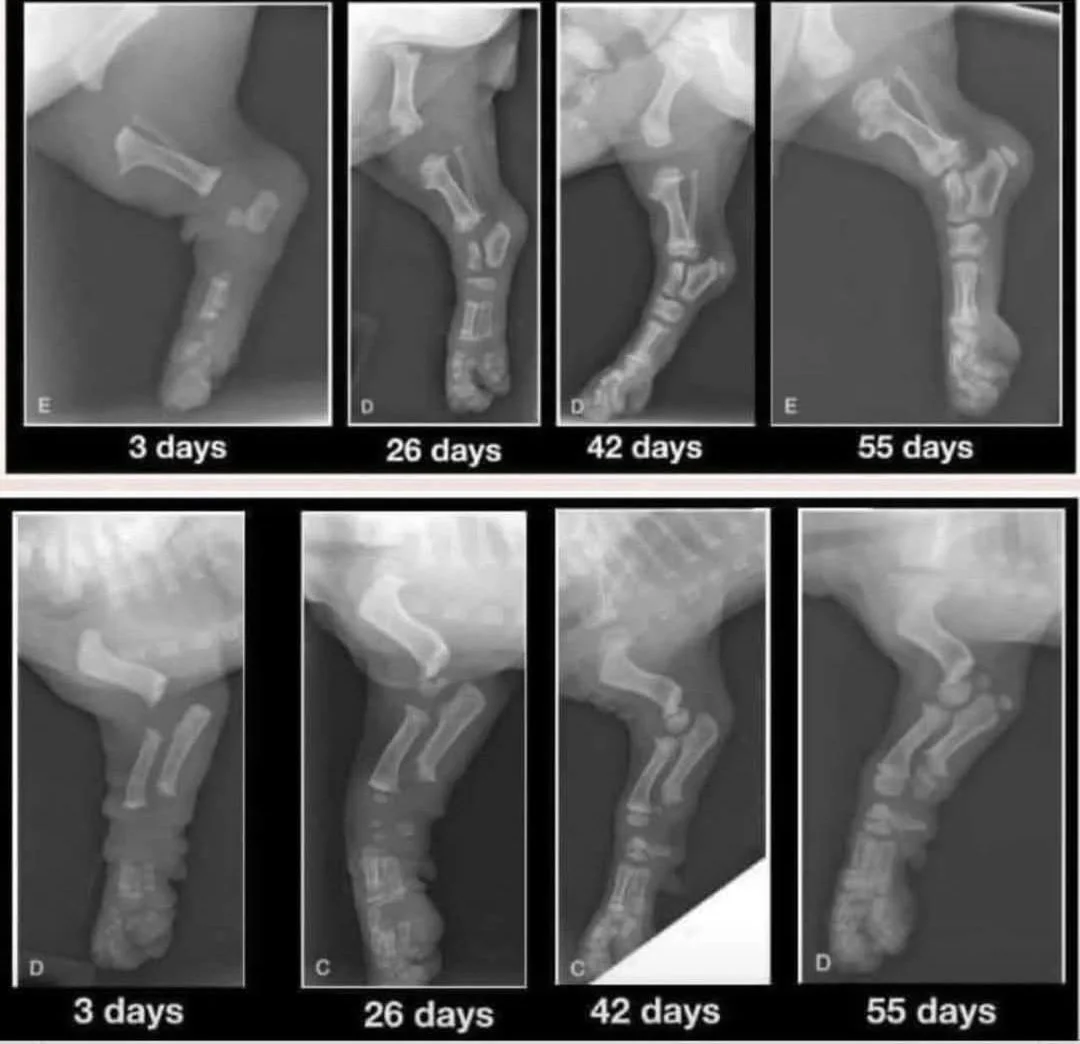

Puppies have growth plates at the ends of their long bones. These areas are soft and cartilaginous, allowing for bone growth. Think of them as the building blocks for your puppy's future skeletal structure. These growth plates remain soft and vulnerable until they calcify and close, which typically happens around 18 months of age, often signaled by sexual maturity.

Before this closure, a puppy's joints are primarily held together by muscles, tendons, and ligaments. This is why puppies often have those adorable, clumsy, and wobbly movements with big floppy paws – their joints don't have the tight, true "socket" fit of an adult dog.

Because growth plates are softer than the surrounding tendons and ligaments, excessive force or impact can easily cause injuries. If a puppy is injured, these strong soft tissues can actually pull apart the delicate growth plates, leading to potentially lifelong issues. Your friend's experience with her Lab puppy falling off a retaining wall is a tragic example of how a seemingly minor incident can have devastating consequences.